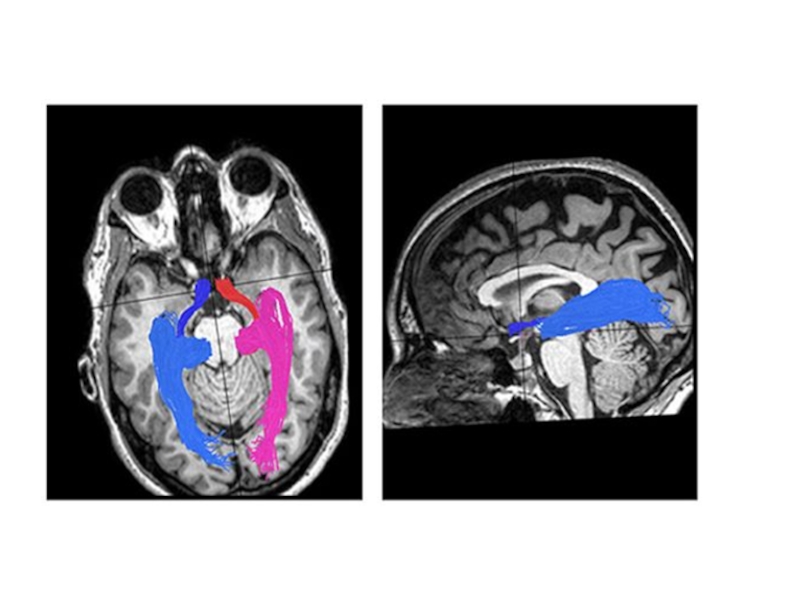

Слайд 6Совокупность аксонов ганглиозных клеток образует зрительный нерв - зрительный перекрест (chiasma

opticum), в котором идут перекрещенные волокна от медиальных (носовых) половин сетчатки, волокна от латеральных (височных половин) идут со своей стороны- зрительный тракт (правый зрительный тракт – волокна от правых половин сетчатки, левый зрительный тракт – волокна от левых половин сетчатки)

4 нейрон – располагается в латеральном коленчатом теле и подушке таламуса

Латеральное коленчатое тело – первичный зрительный центр

Аксоны 4 нейрона образуют зрительную лучистость (пучок Грасиоле) в коре затылочной доли

Корковая зона зрения – верхний (принадлежит клину) и нижний край (принадлежит язычной извилине) шпорной борозды (sul.calcarinus) на медиальной поверхности затылочной доли